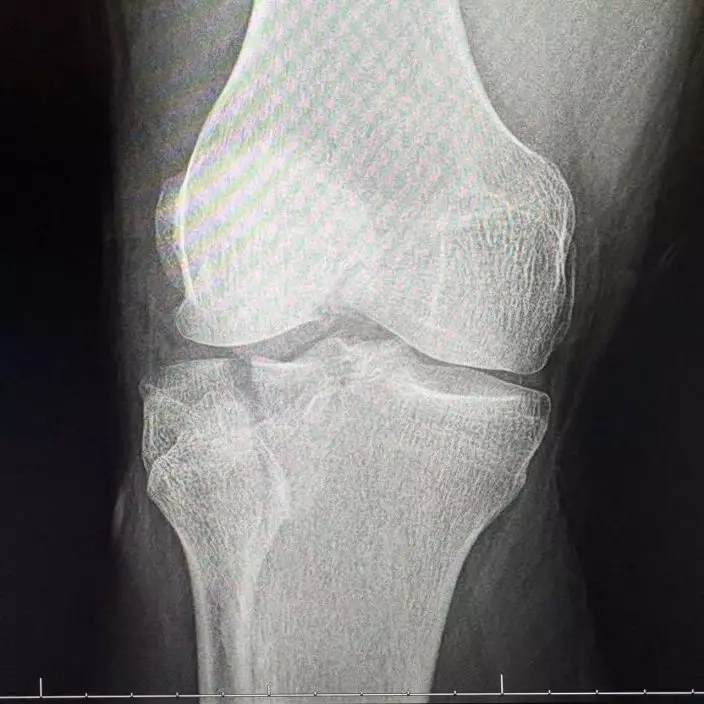

哈里斯被救出時已出現腿部骨折及嚴重失溫情況,同時伴隨肺炎、肺部挫傷及腎臟受傷等傷勢,隨即被送往醫院接受治療,目前仍在康復中。親友事後於募款網站上表示,哈里斯已完成手術,恢復情況良好,並感謝外界的關心與支持。哈里斯也透露,事發時自己的手機其實就在身旁,但始終無法伸手取得。他直言,若非妻子透過定位功能追蹤位置並及時求助,自己很可能已經無法生還。